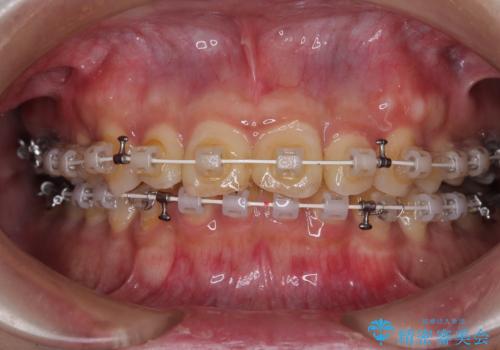

補助装置を用いて、上顎大臼歯を積極的に後方移動させながら、ディープバイトを改善していくこととしました。

強い咬合力に抵抗するため、上下ともに表側のワイヤー装置にて矯正治療を行うこととしました。